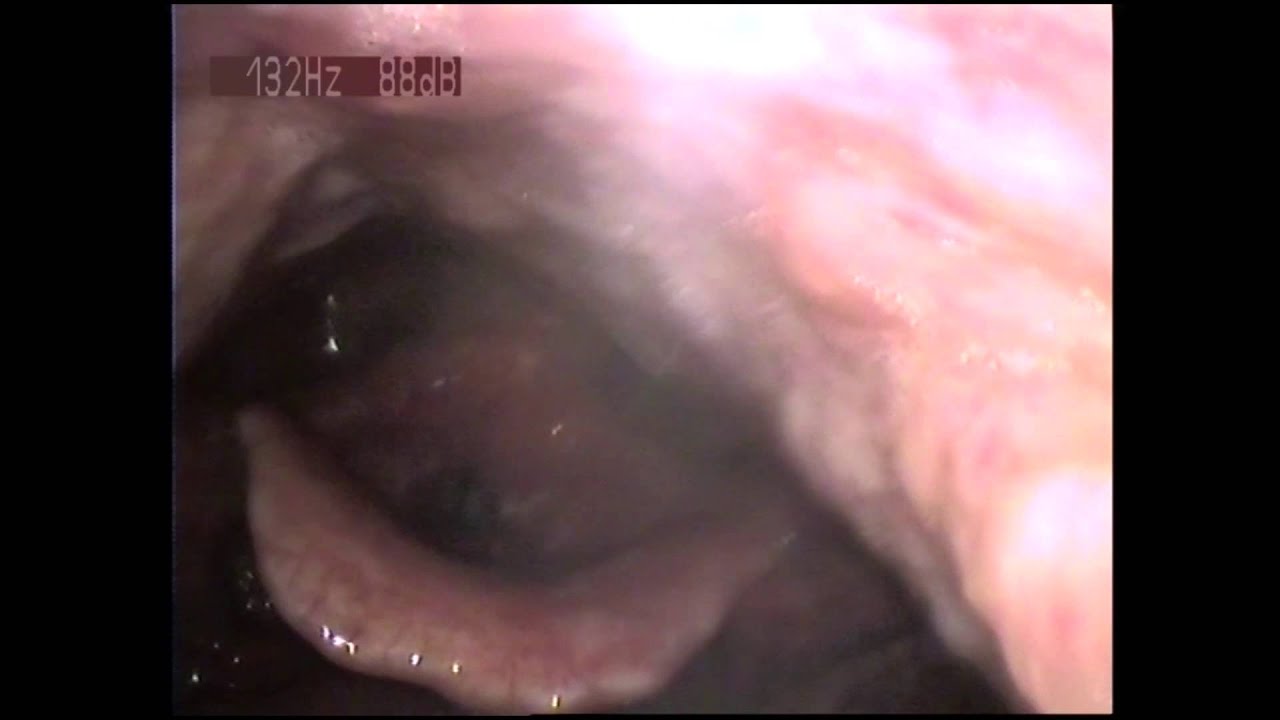

What a beat boxer’s vocal folds look like

https://www.youtube.com/watch?v=faAtOul8euQ http://bit.ly/2LrpozR